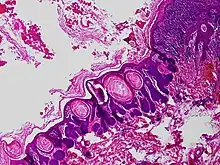

Trichofolliculoma is a cutaneous condition characterized by a benign, highly structured tumor of the pilosebaceous unit.[1][2] Trichofolliculoma is a rare tumor of the eyelid. It can be suspected by the “cotton bag sign”[3]